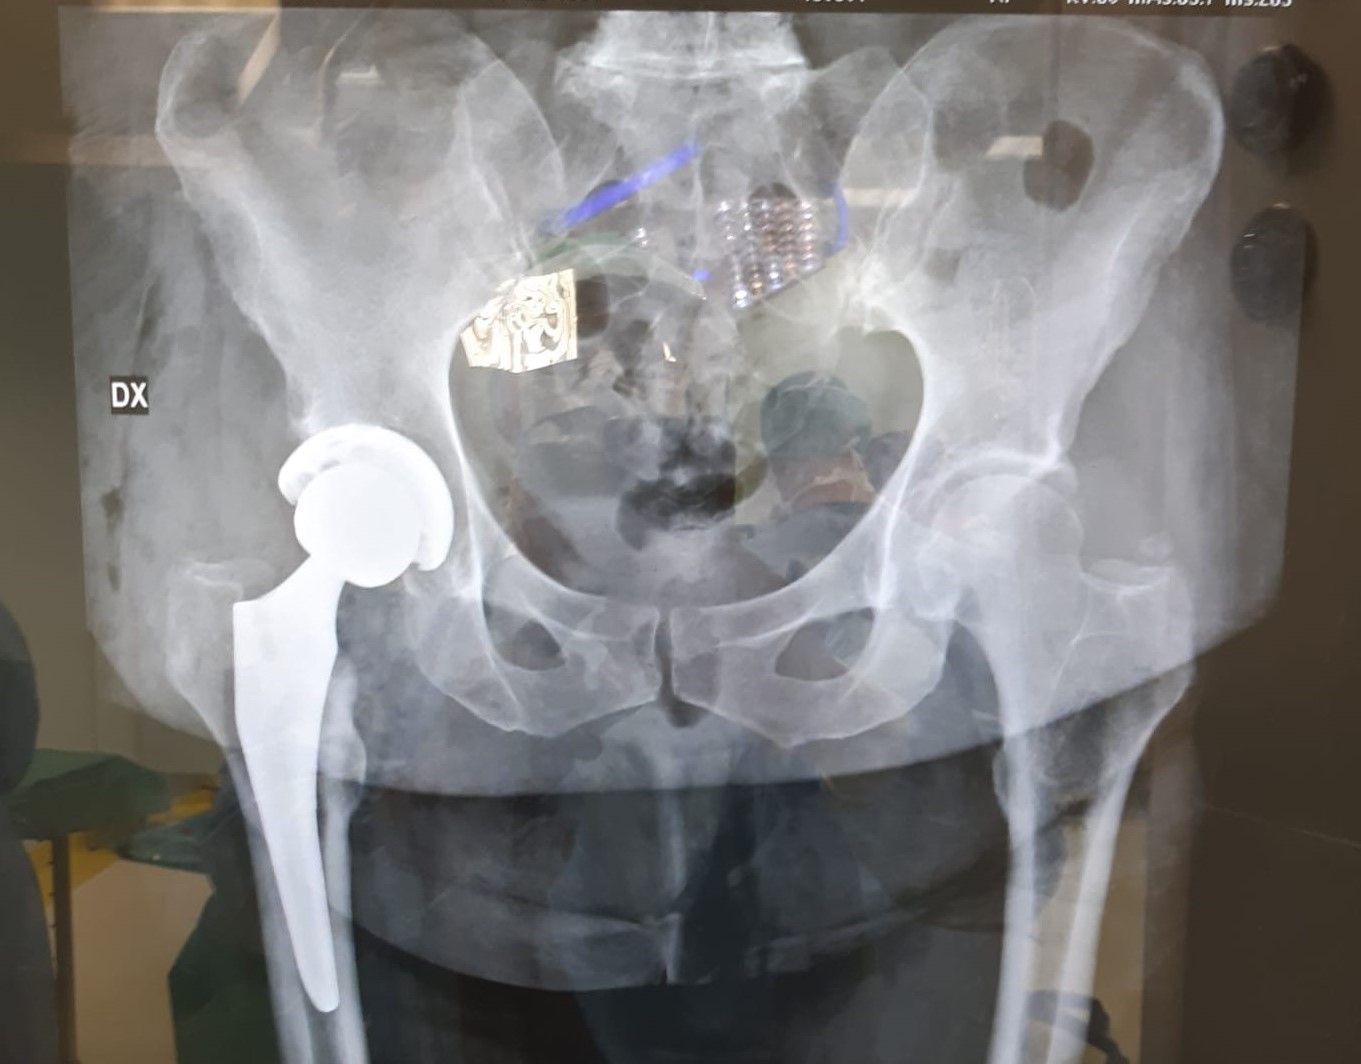

L’operazione viene effettuata attraverso un’incisione praticata all’altezza dell’anca. La testa del femore viene rimossa e la cavità viene preparata ad accogliere una superficie artificiale detta protesi. La testa e il collo del femore sono sostituiti con una protesi di metallo di alta qualità, mentre la cavità viene sostituita con un guscio di metallo rivestito da plastica chirurgica ad alta densità.

A seconda del tipo, può essere necessario cementare la protesi all’osso: alcuni tipi di protesi, invece, non devono essere cementati, perché l’osso circostante cresce all’interno della protesi e la cementa autonomamente. Alla fine dell’operazione la pelle viene ricucita e per, rimuovere l’eventuale liquido in eccesso, può essere usato un drenaggio.